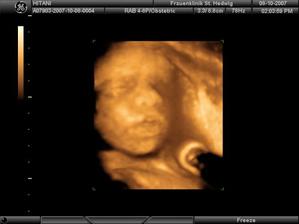

Narodila sa 29.12.2007 o 23.02 hod v klinike sv. Hedvigi v Regensburgu (Nemecko) s nadhernymi mierami: 50cm, 3280g a obvod hlavicky 33,5cm....